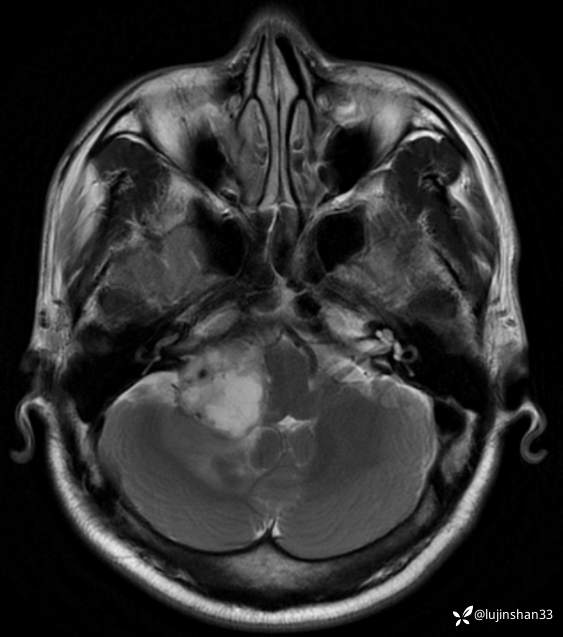

术前CT及MRI

临床诊断:右侧桥小脑角血管母细胞瘤

讨论:桥小脑角区占位,血供情况如何判定?良恶性如何从影像学判定?